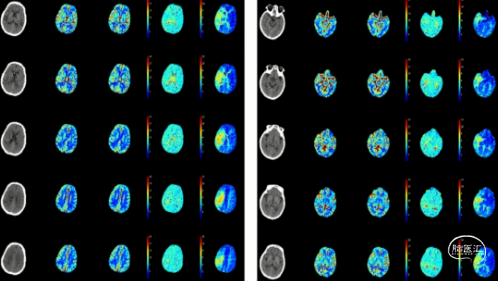

CTP(2023.06.26/本院):右侧额顶叶、半卵圆中心见片状灌注延迟区,TTP、MTT延长,CBF减低

3.当地脑MRI回示右侧大脑半球多发梗死灶,脑血管造影回示责任血管右侧颈内动脉起始处段、颅内段和右侧大脑中动脉起始段重度狭窄,入院后高分辨提示动脉粥样硬化改变,脑CTP回示右侧大脑半球低灌注,ASITN分级:2级,需行手术治疗改善狭窄,从而预防脑卒中、认知障碍等,手术指征明确;